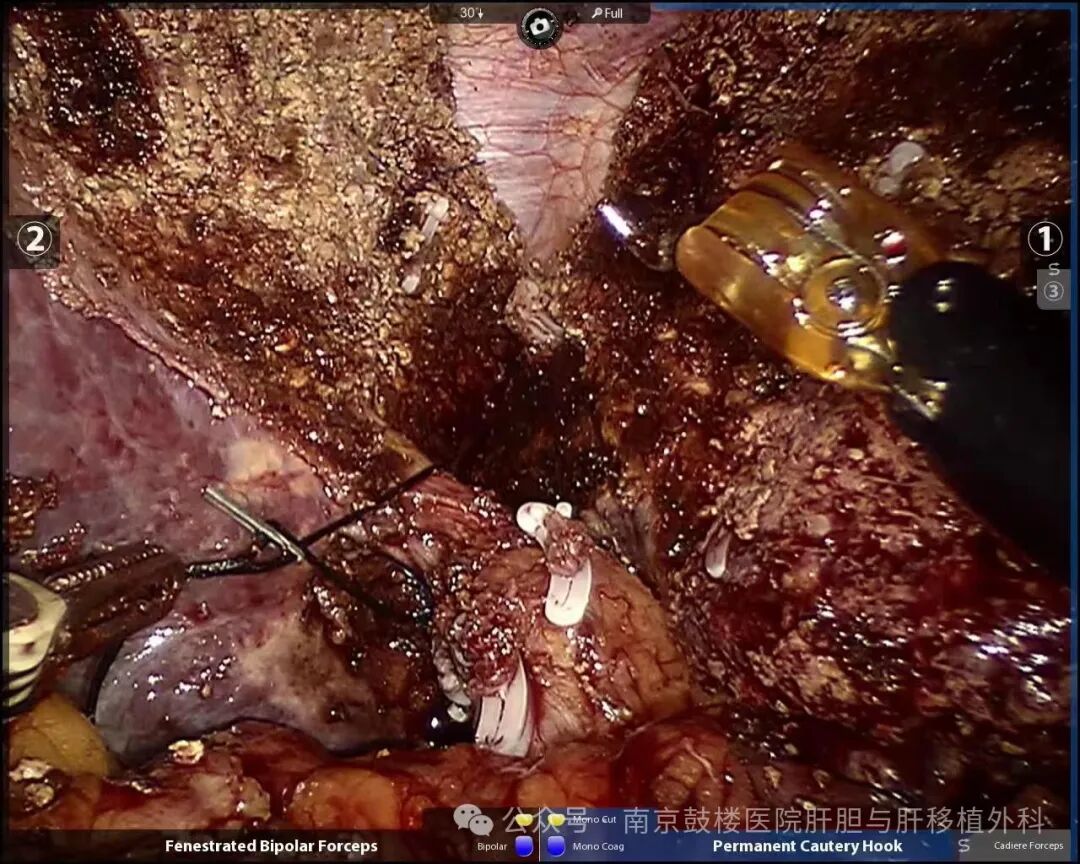

5月30日,患者接受了一期手术,余德才教授带领团队,借助手术机器人将患者左右肝实质完全劈开,离断门静脉右支,有效阻断左右肝脏之间的交通血流,精细处理肝断面的管道。